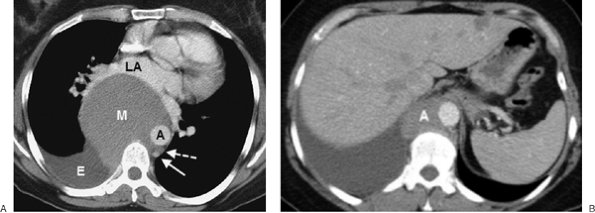

FIGURE 6-16. Benign teratoma. A: PA chest radiograph shows abnormal opacity in the right hemithorax, some of which is caused by pleural effusion, and mediastinal shift to the left. B: Lateral view shows abnormal opacity in the retrosternal area. C: CT scan shows an anterior mediastinal mass of homogeneous soft tissue attenuation (M), compressing a narrowed superior vena cava (solid arrow) and right pulmonary artery (dashed arrow), and right pleural effusion (E).